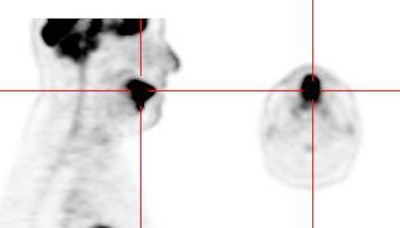

|

Head and neck activity: The images below show typical uptake in the tonsils (black arrows), submandibular glands (blue arrows), and parotid glands (red arrows) |